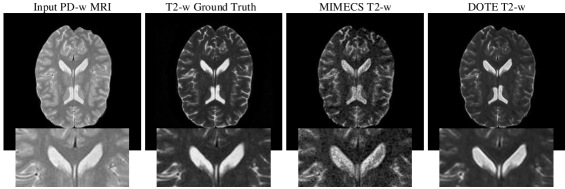

Cross-Modality Synthesis. For the problem of CMS, we evaluate DOTE and the relevant algorithms on both datasets involving six groups of experiments: (1) synthesizing T2-w image from PD-w acquisition and (2) vice versa; (3) generating T1-w image from T2-w input, and (4) vice versa. We conduct (1-2) experiments on the IXI dataset, while (3-4) are explored on the NAMIC dataset. The representative and state-of-the-art CMS methods, including Vemulapalli’s method [3] and MIMECS [11] are employed to compare with our DOTE approach. We demonstrate visual and quantitative results in Fig. 4, Fig. 5 and Table. 3, respectively. Our algorithm yields the best results against MIMECS and Vemulapalli for two datasets validating our claim of being able to synthesize better results through the expanded dual optimization.

Refer to caption

Figure 4: Visual comparison of synthesized results using MIMECS and DOTE.